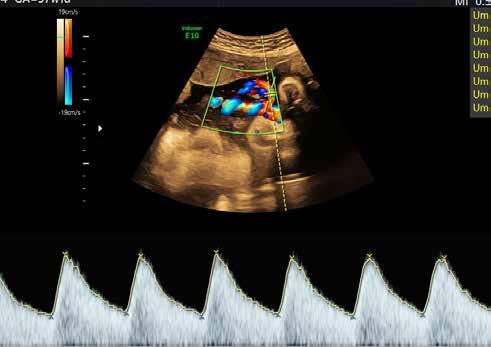

Die Blutversorgung der Plazenta

Dafür gibt es ein spezielles Ultraschallverfahren, dass den Blutstrom und den Fließwiderstand sichtbar macht. Beides entscheidet darüber, ob das Kind gut versorgt wird. Sollte dies nicht der Fall sein, gibt es Handlungsmöglichkeiten.

„Bis zur 34. Schwangerschaftswoche geben wir Müttern zweimal innerhalb von 48 Stunden ein

Glucocorticoid“, sagt der Klinikdirektor. Damit wird die Organreife der Lunge des ungeborenen Kindes angeschoben – eine Voraussetzung, um eine eventuelle Geburtseinleitung oder einen Kaiserschnitt in Erwägung ziehen zu können.

Bestimmte Ultraschallgeräte können auch die Richtung und Geschwindigkeit bestimmen, mit der das Blut durch die Blutgefäße oder das Herz strömt. Dies wird Doppler-Untersuchung genannt.